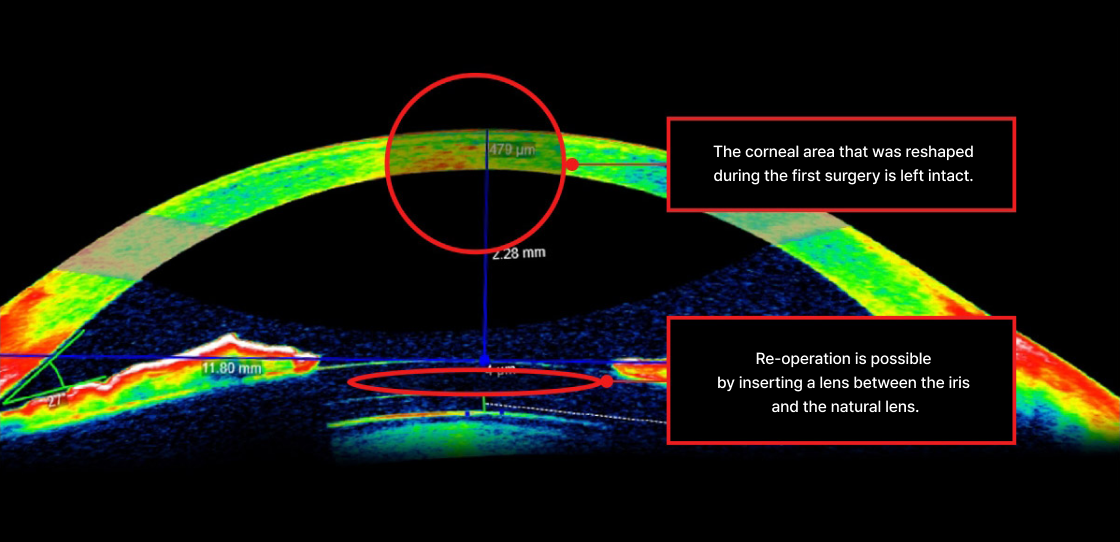

No need to alter

the modified cornea

Minimal risk of

regression recurrence

No epithelial ingrowth

complications

corneal haze

Reduced risk of

dry eye symptoms

Extremely low risk

Of keratoconus